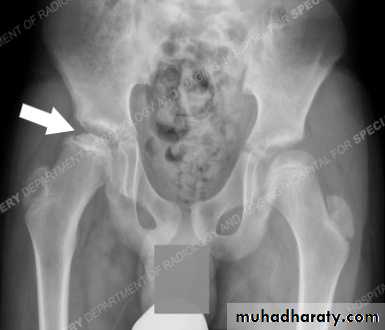

X-ray

1- at the beginning the x- ray look normal some time we can see asymmetry of the ossific centers ; bone scan is helpful at this stage (showing the avascular area) .

2- later on the increase density of the ossific nucleus will be clear ; and there is increase in the joint space .

3- fragmentation of the epiphysis .

4- flattening and lateral displacement of the epiphysis .5- widening of the metaphysis .

6- in sever and advance cases the head become mushroom shape .

Criteria of ahead at risk

1- progressive uncovering of the epiphysis

2- calcification of the cartilage lateral to the ossific nucleus .

3- radiolucent area at the lateral edge of the epiphysis .

4- sever metaphyseal resorption .